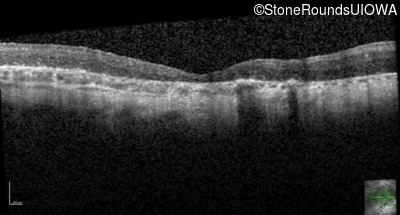

Age at visit: 31 years

Age at visit: 33 years